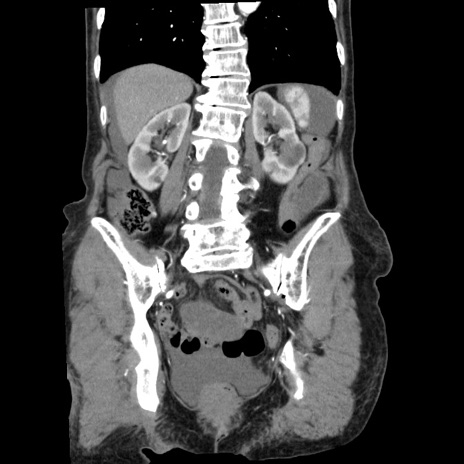

横断像